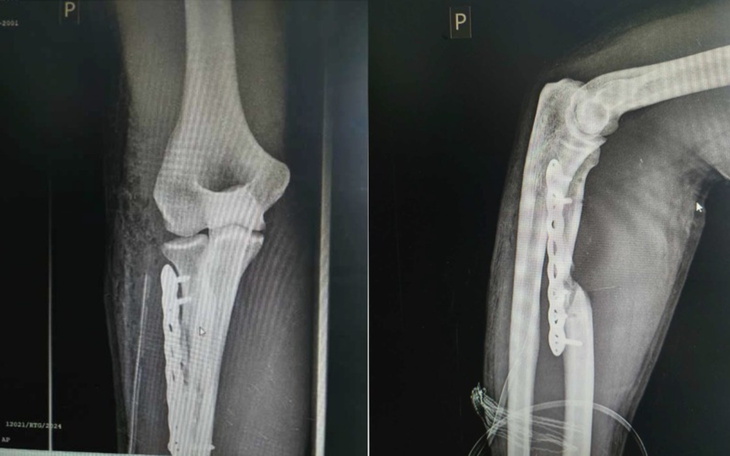

Zamiast ratunku – "oskalpowanie". Pierwsza operacja w ZCO w Dąbrowie Górniczej była początkiem drogi przez piekło. Obudziłem się z bólem, którego nie da się opisać, i dłonią, która była bezwładna. Kiedy sam, na własną rękę, wyprosiłem zdjęcie RTG, przeżyłem szok: kości krzywo ułożone osiowo, śruby wyrwane, płyta stabilizująca wisząca bez stabilizacji, porażenie nerwu powodujące całkowite zwiotczenie dłoni, uszkodzone ukrwienie. Ortopedzi w innym szpitalu nie przebierali w słowach: zostałem "oskalpowany", a moja ręka wyglądała jak po wybuchu bomby. Lekarz operujący wyjmował śruby palcami.. To wszystko spowodowało, że moja kość zamiast się zrastać przez kolejne miesiące tylko obumierała..

Ponad rok w matni bólu i upokorzenia. Ta jedna „zwykła” operacja spowodowała, że moja kość stale obumierała powodując 3 cm ubytku w kości co widać na RTG przedstawiającym rękę na luty 2025 już po dwóch operacjach (zepsuta w ZCO DG i naprawiająca w Szpitalu Miejskim w Sosnowcu. Do 29.01.2026, przez ostatnie półtora roku przeszedłem poważne 3 operacje stabilizacji kości, w tym jedną z przeszczepem kości z biodra do ręki oraz 1 zabieg biopsyjny - dodatkowe wiercenie drugiego biodra i bolesne ostrzykiwanie szpikiem biopsyjnym, serii ostrzyknięć komórkami wzrostowymi, niekończącą się rehabilitację i zabiegi, przy których ból do prowadzał do utraty przytomności. Co tydzień jestem podpinany pod bardzo nieprzyjemny prąd aby naprawić porażony nerw. Miałem być oparciem dla bliskich, a stałem się człowiekiem, którego partnerka musi myć gąbką na stołku, bo sam nie jest wstanie ustać z bólu, oraz pomagać mi w codziennej egzystencji. To upodlenie, którego nie życzę nikomu, zwłaszcza gdy masz całe życie przed sobą. Miałem być oparciem a stałem się ciężarem, którego sam nie mogę unieść..